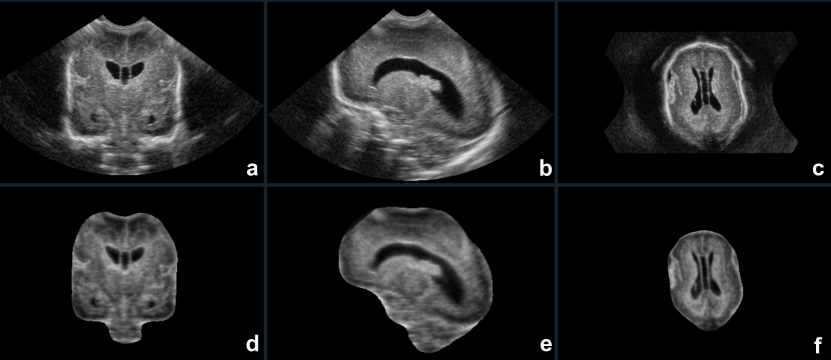

The results demonstrate a strong correlation between observed and predicted total brain volume, indicating the effectiveness of the proposed method in accurately estimating total brain volume from 3D ultrasound images. In addition, Table 6 provides performance evaluation using HUPM 3D ultrasound data, demonstrating high DICE (F1) score, low MSD, and high recall and accuracy rates. Figure 6 illustrates a 3D ultrasound (US) image along with the corresponding reconstruction and segmentation outcomes obtained with the proposed MGA-Net and applied to a real ultrasound image sourced from the HUPM dataset. Visualization was performed using MELAGE software.

For the ultrasound (US) datasets, Figure 10 presents coronal, sagittal, and axial view of a 3D ultrasound from the HUPM dataset, displaying the image before and after processing with the MGA-Net. This figure illustrates the effectiveness of the proposed method in reconstructing images, highlighting how MGA-Net enhances the visual quality and detail for better diagnostic evaluation.

Refer to caption

Figure 10: 3D Ultrasound (US) image of a preterm neonate born at 28.29 gestational weeks, imaged at 29 weeks: Top) Original US image, Bottom) US image processed with MGA-Net. Coronal, sagittal, and axial sections are displayed from left to right.